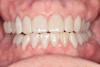

After the restorations were milled, they were sintered and polished for final effect. It was decided that these restorations should not be glazed to avoid the added abrasivity that accompanies this finish to the restoration.22 The patient was then scheduled for temporary crown removal. The final crowns were fitted on the prepared teeth, and the contacts adjusted. The patient reported that she was pleased with the feel and esthetics of the restorations, and the restorations were cemented (Figure 14 through Figure 19).

Fig. 14